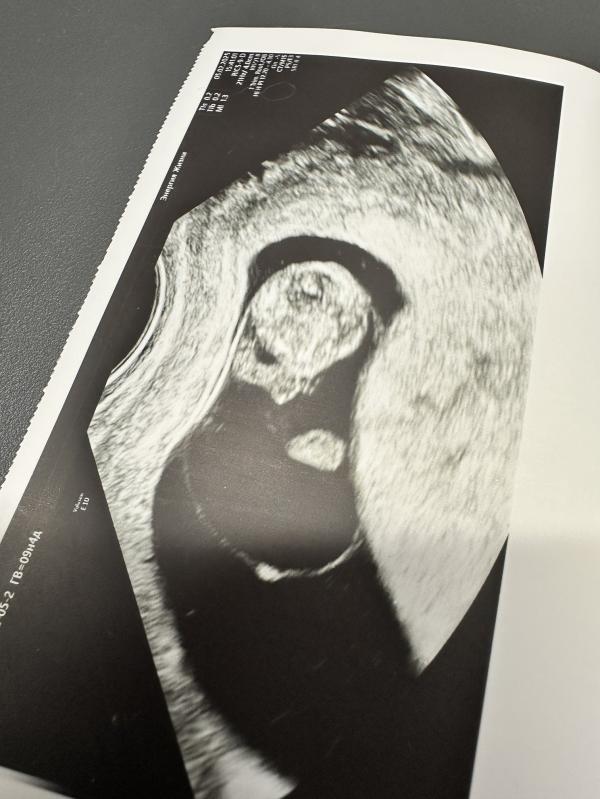

Разглядели сегодня все что могли 🙂 , мозг, сердце, позвоночник, уши, ручки с ножками и даже пальчики 🥹 эмоции не передать… 🥰

на снимок (последнее фото) удалось запечатлить ручку с пальчиками ✌️😅